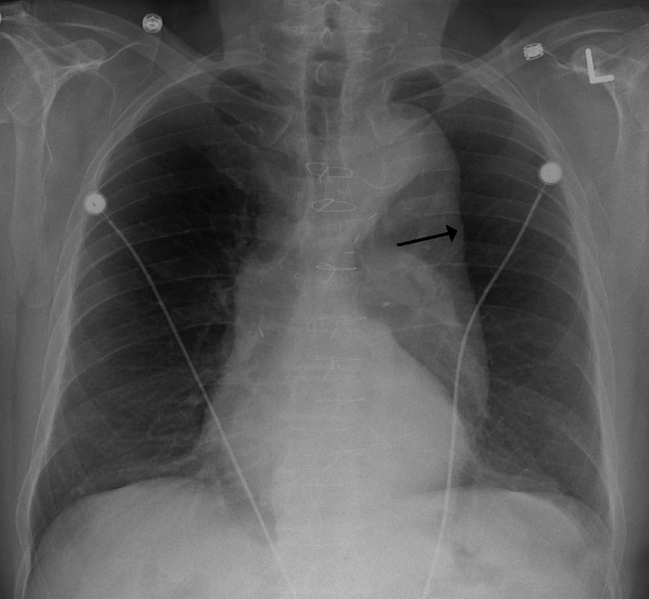

- Radiografías simples

Las radiografías simples de tórax, abdomen o columna vertebral, generalmente aportan suficiente información para establecer el diagnóstico inicial. Los aneurismas que se localizan en la aorta ascendente generan una sombra convexa del lado derecho de la silueta cardiaca, si hacemos una proyección lateral, se puede ver obliteración del espacio retroesternal en el caso de los aneurismas que se extienden en sentido anterior.

Imagen de Dominio Público CC-BY-SA-3.0. Autor: James Heilman, MD. Fuente

Luego que se ha logrado detectar un aneurisma con una radiografía simple, se debe realizar estudios adicionales para determinar la extensión de la lesión.